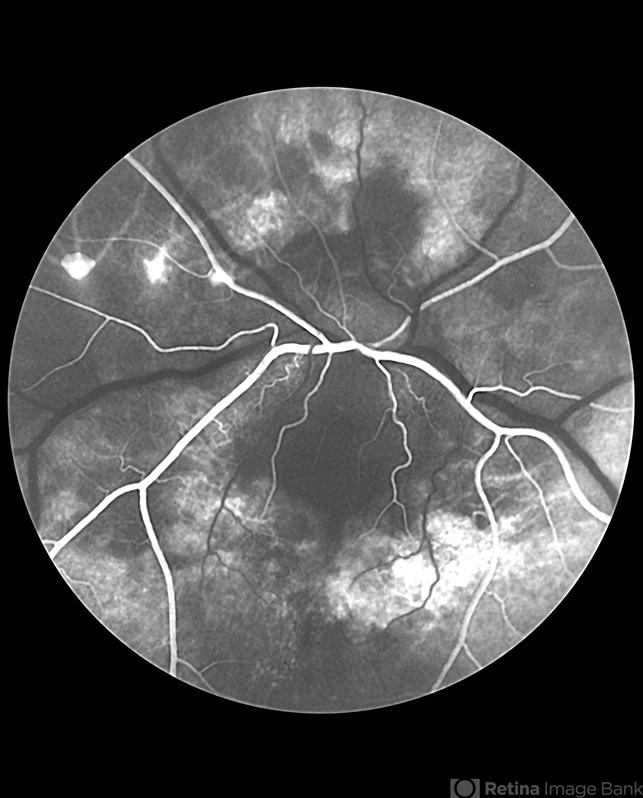

- No history or color photos. Fluorescein angiogram sequence.